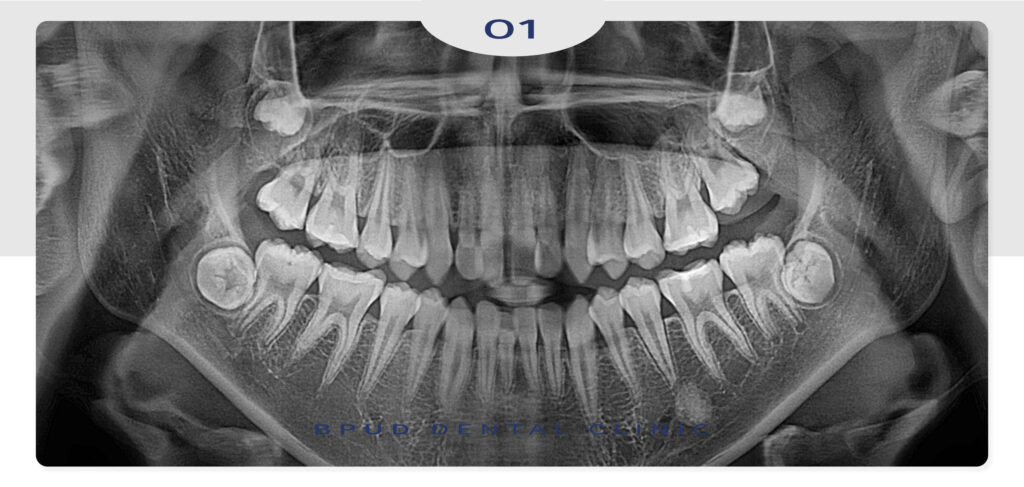

오늘은 부정교합으로 앞니가 많이

삐뚤빼뚤했던 학생 환자분이

부평치과에서 클리피씨 교정으로

해결한 사례를 소개해 드리려고 합니다.

발치를 하지 않고 전체적으로

클리피씨 교정을 진행하기로 하였고

추후 사랑니 발치를 진행하기로 하였습니다.

2023.09.21